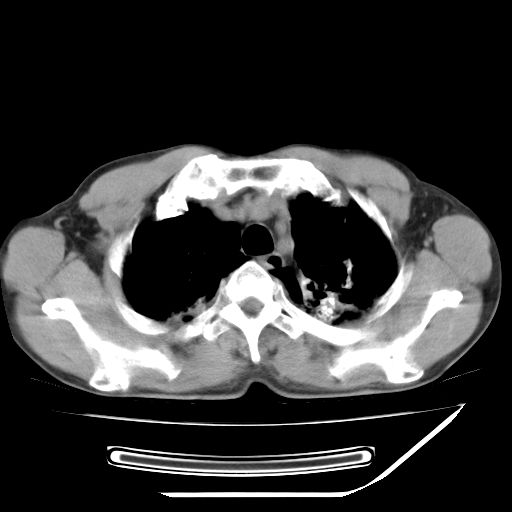

男,59岁,“结核性胸膜炎”30余年,胸部经常疼痛,多次x检查提示“肺部”炎症。腹部疼痛5日,b超提示:“肝内短管结石,余显示不清,建议进一步检查。”

两肺结核并右侧胸腔积液;脾脏、腹腔及腹膜后淋巴结结核[陈旧性];肝内胆管结石

胸部腹部都是结核(双肺。纵隔淋巴结,肝脏,脾脏,肠系膜)